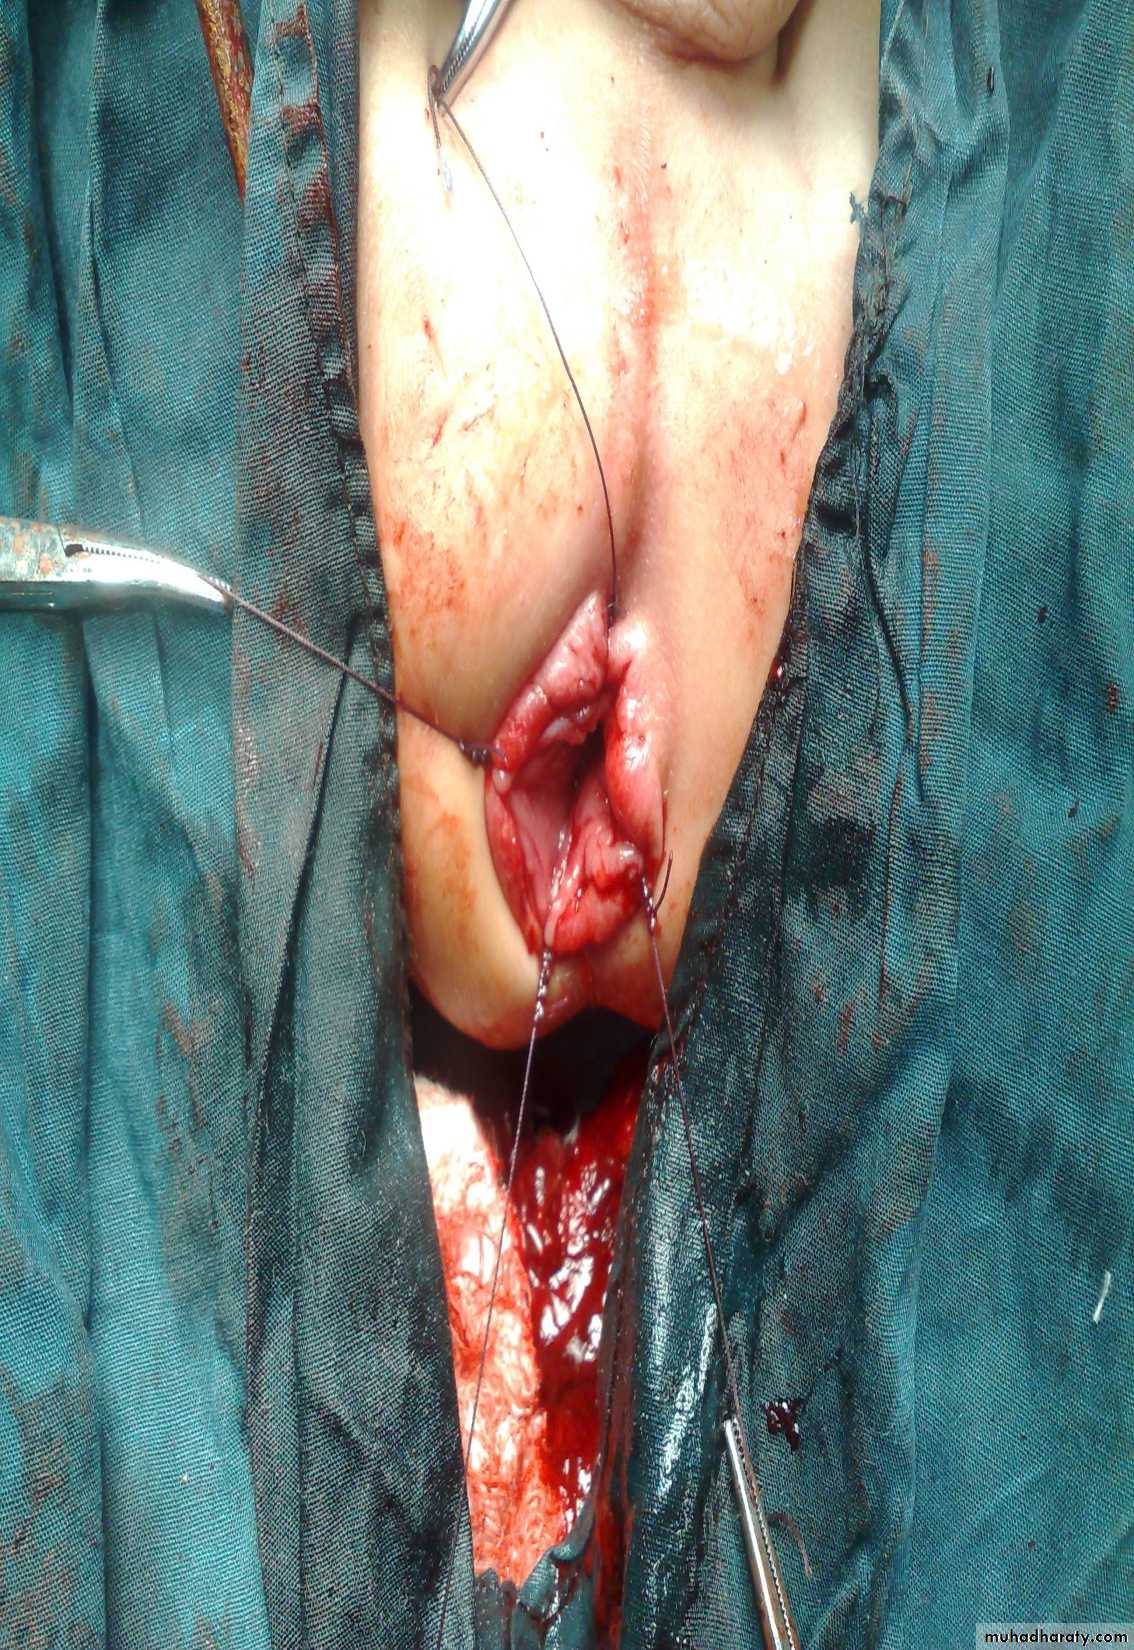

Defect=sac